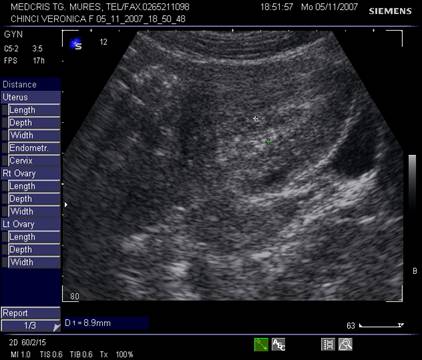

Fig nr. 91. Nodul fibromatos submucos si sarcina

Fig. nr. 92. Nodul fibromatos intramural hipoecogen,

alaturi de sarcina de 12 saptamani